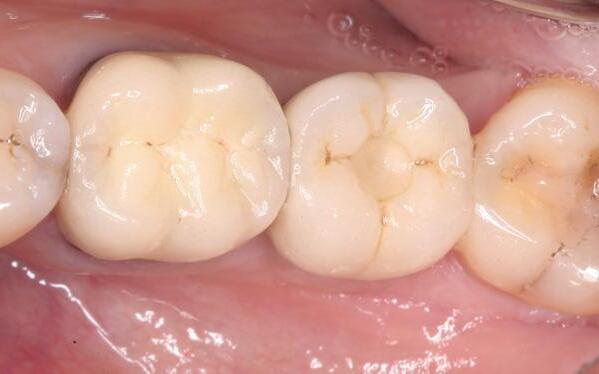

In afbeeldingen 4a-c is het resultaat drie maanden na het plaatsen van het implantaat te zien. De genezing is volledig en de verwijzer kan de suprastructuur vervaardigen (afbeelding 4a-4c).

In afbeeldingen 5a-d is de implantaatkroon 37 te zien, twee jaar na plaatsing. Op de röntgenfoto is herstel van zowel corticaal als spongieus bot te zien. (De CB-CT was vervaardigd in verband met implantologische indicatie in het naastliggende gebied).

Deze casus illustreert dat er op een voorspelbare manier een ridge preservation procedure uitgevoerd kan worden met een d-PTFE membraan en er daarna voorspelbaar geïmplanteerd kan worden.